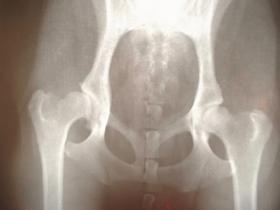

機能性身体症候群とは、疲労感、頭痛、関節痛、筋肉痛、動悸、めまい、腹痛、下痢などの身体の不調が続いているにも関わらず、臨床検査(X線やCTなど)の異常所見が見当たらない、近年提唱された新しい疾患概念です。

西洋医学での判断は画像によるものがメインです。そのため、画像に映らないコリに対して語られることはあまりなく、画像に異常がない場合は改善に対する方法すら取られませんでした。しかしCNMSと呼ばれる病気の頚性神経筋症候群という名前ができ、今は西洋医学でも認められています。